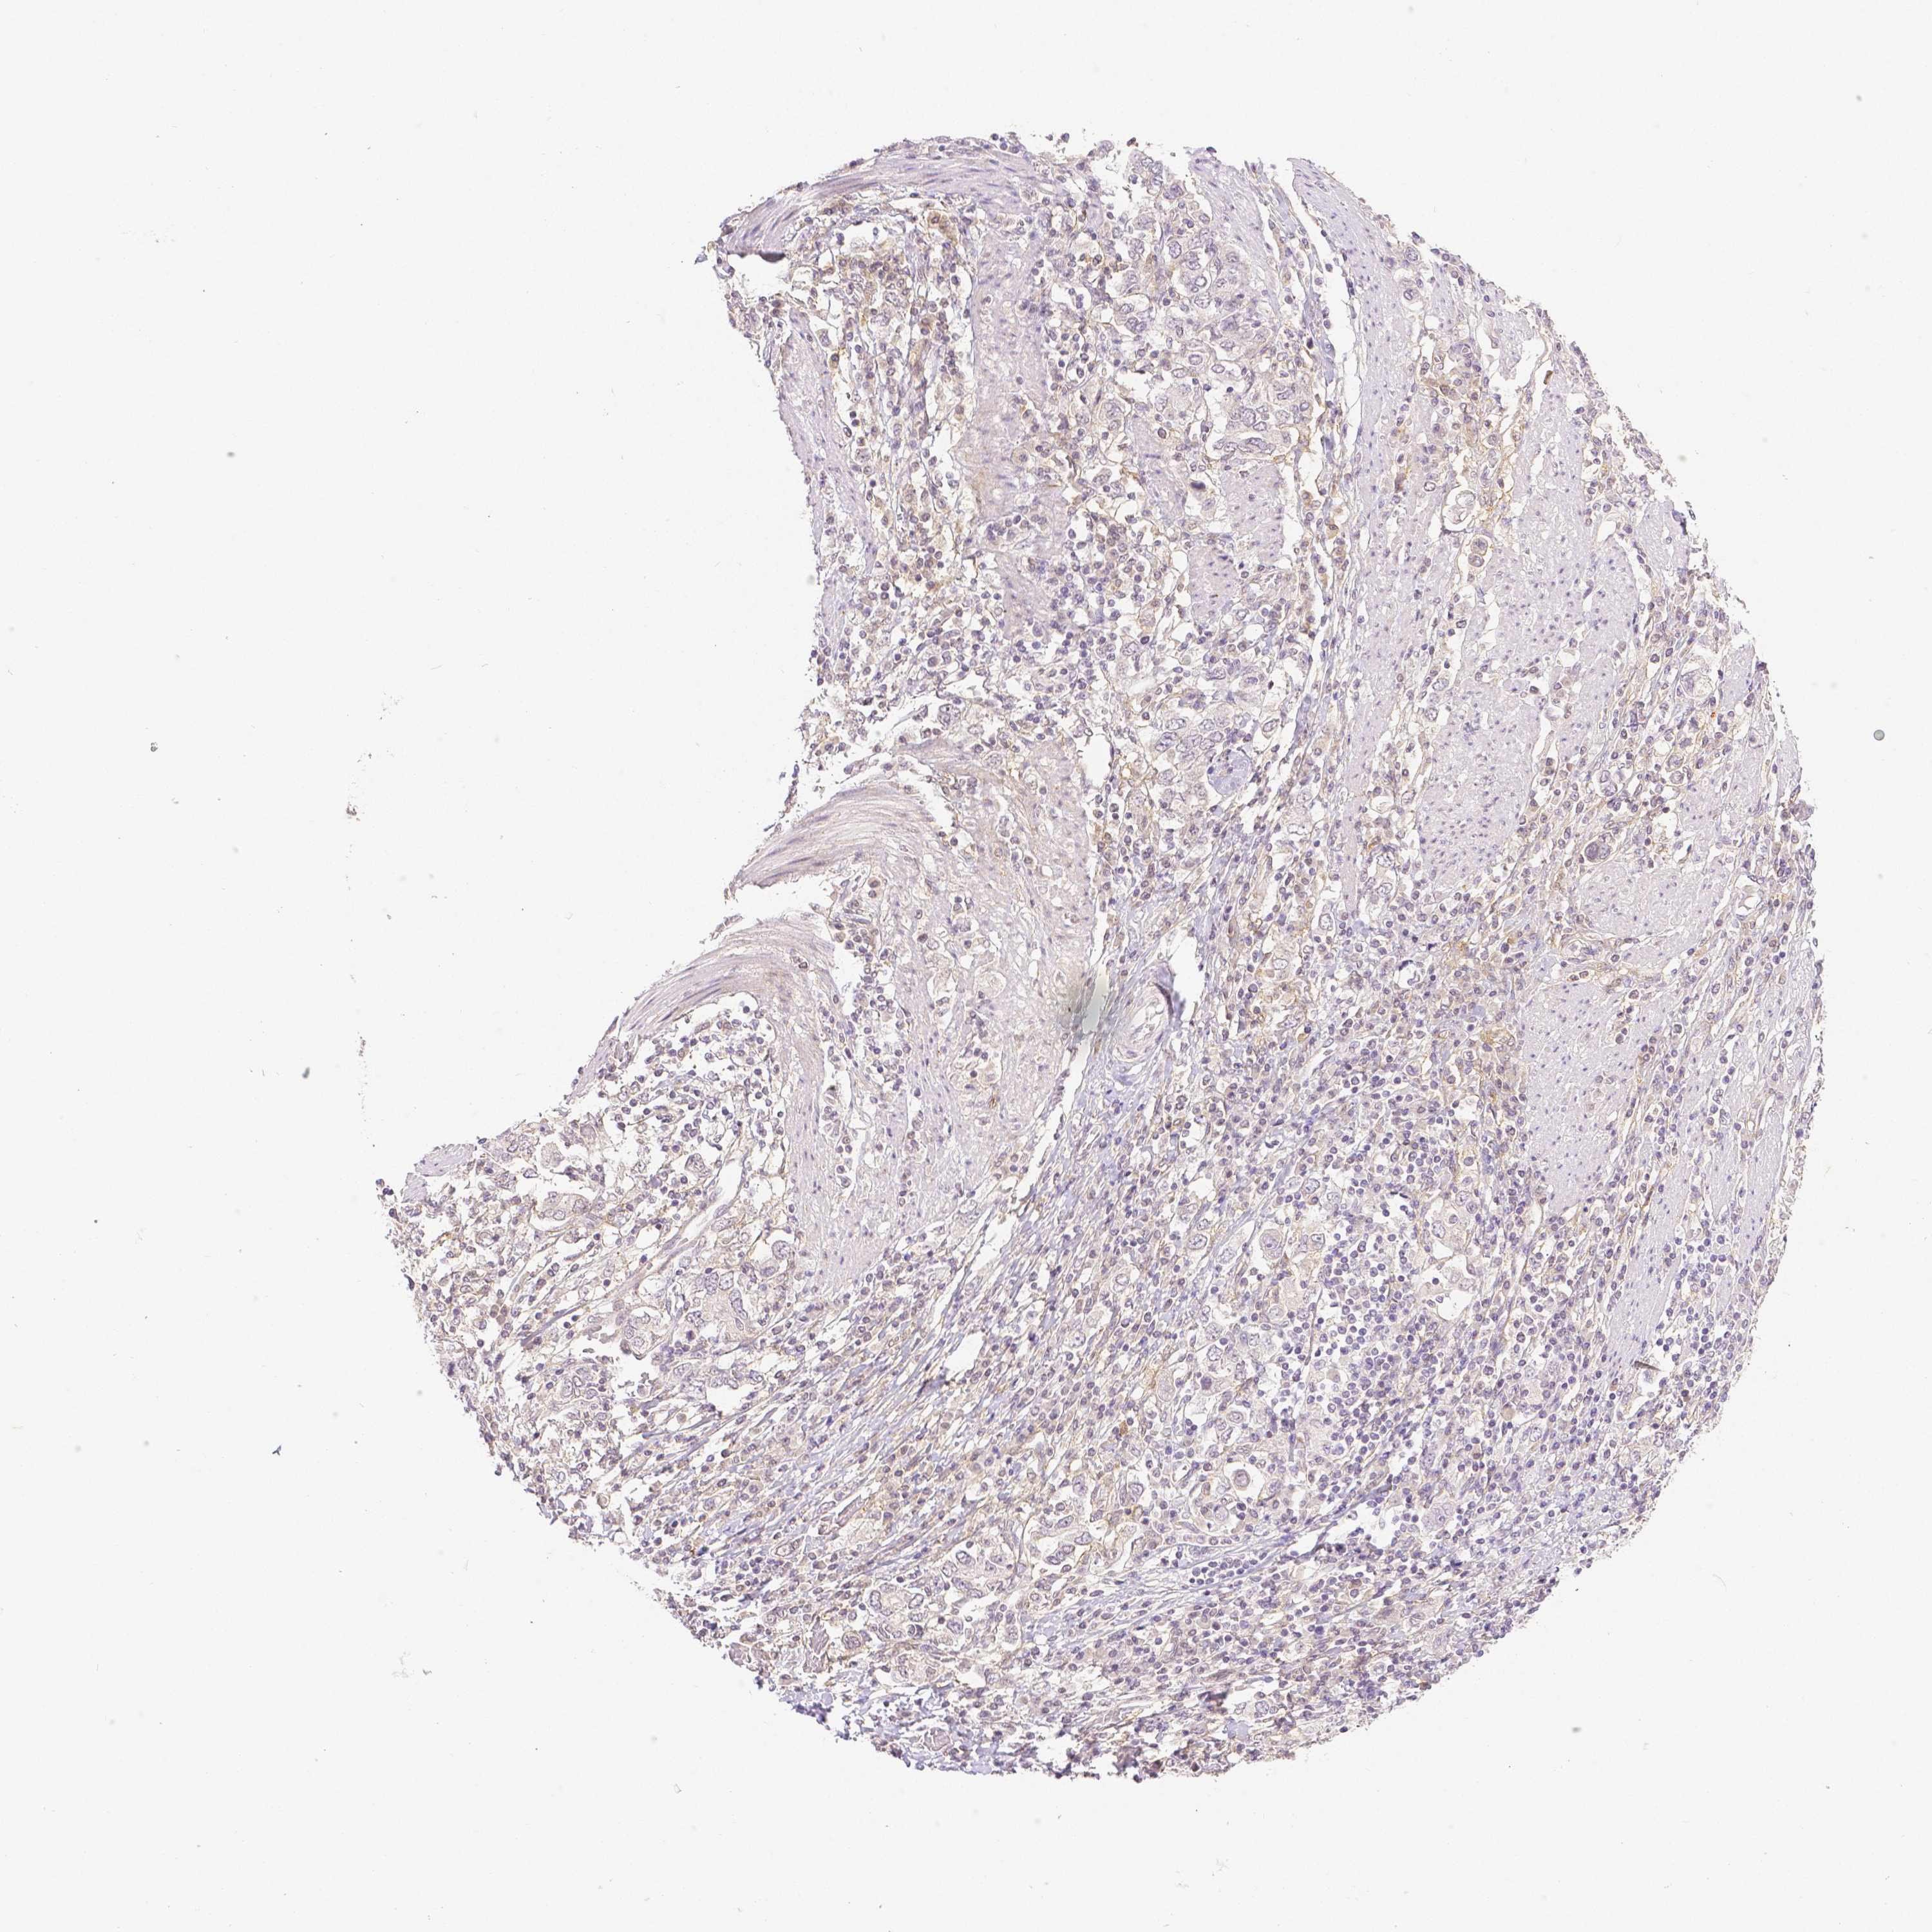

STOMACH CANCER - Protein expressioni

A mouse-over function shows sample information and annotation data. Click on an image to view it in a full screen mode. Samples can be filtered based on level of antibody staining by selecting one or several of the following categories: high, medium, low and not detected. The assay and annotation is described here.

Antibody stainingi

Antibody staining in the annotated cell types in the current human tissue is reported as not detected, low, medium, or high, based on conventional immunohistochemistry profiling in selected tissues. This score is based on the combination of the staining intensity and fraction of stained cells.

Each image is clickable and will lead to virtual microscopy that enables deeper exploration of all samples and also displays staining intensity scores, fraction scores and subcellular localization as well as patient and tissue information for each sample.

Antibody HPA003733

Antibody CAB068243

Antibody CAB068244

Staining

High

Medium

Low

Not detected

Intensity

Strong

Moderate

Weak

Negative

Quantity

>75%

75%-25%

<25%

None

Location

Nuclear

Cytoplasmic/membranous

Cytoplasmic/membranous,nuclear

Adenocarcinoma, NOS